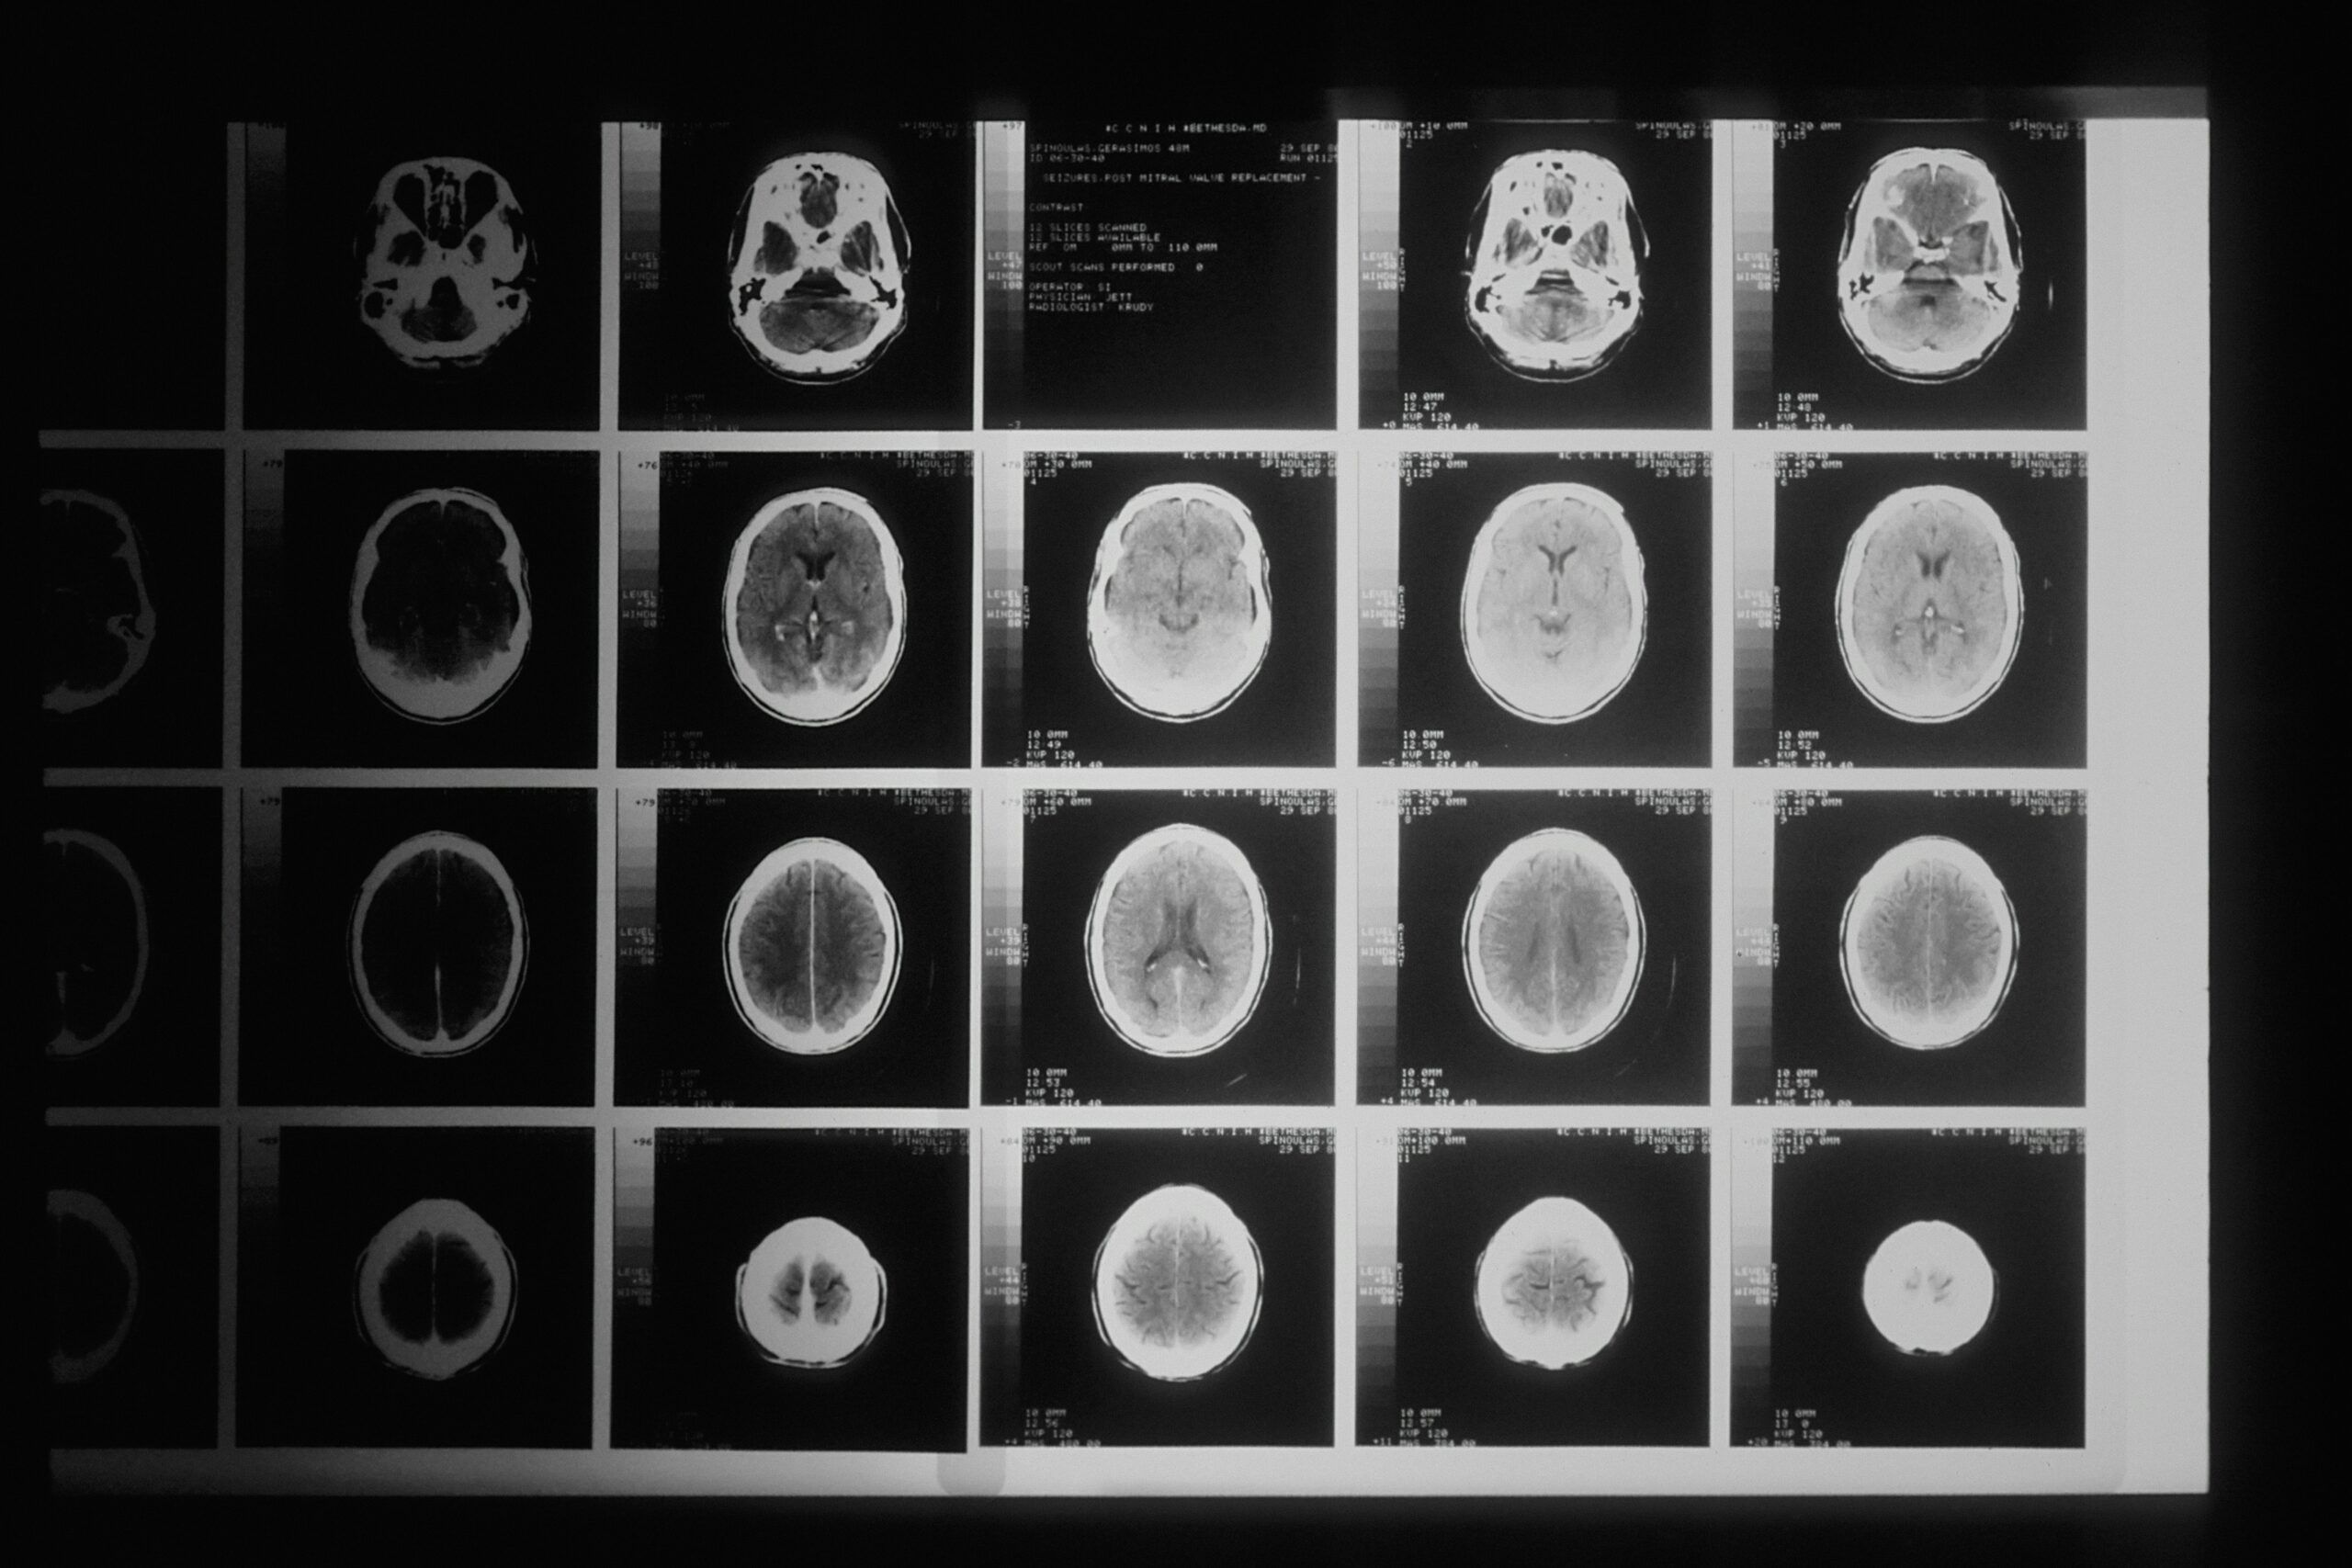

Signs of a Traumatic Brain Injury After a Car Accident

Many people walk away from a car accident believing they are “just shaken up.” In reality, some of the most serious brain injuries begin quietly—without immediate pain, visible trauma, or a loss of consciousness. Recognizing the early signs of a traumatic brain injury (TBI) after a car accident can protect...